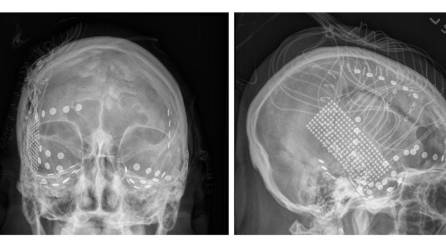

Electrodos registraron señales del cerebro de pacientes con epilepsia mientras escuchaban “Another Brick in the Wall”.

Recrean una canción del cerebro

Al comprender mejor cómo el cerebro metaboliza la música, los científicos esperan construir nuevas “prótesis del habla”.